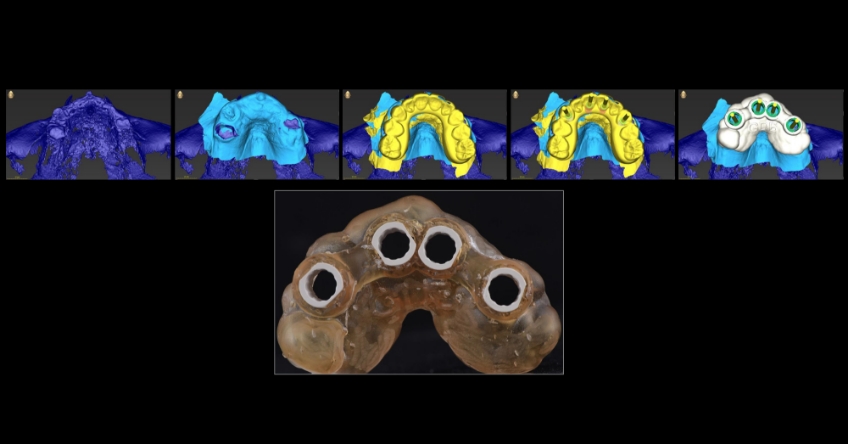

Once the patient understood the nuances between graft vs. a graft-less solution, she opted for a combination of anterior and ZIs instead of grafting the sinuses.

Ultimately, the patient was treated using a combination of traditional and zygomatic implants, allowing her to transition into the definitive prosthesis uneventfully and in a reasonable time frame. This prosthetic design aimed to improve the distribution of occlusal forces and provide enhanced structural support for the final prosthesis.

Comparing zygomatic implants (ZI) vs. bone grating can affect the outcome for your patient. The selection of the proper combination of traditional and ZIs is based on the amount of residual maxillary alveolar bone, the biomechanical requirements of the final dental implant rehabilitation, finances, and surgeon and restorative dentist preferences and experience. The most critical factor for success is the establishment of a prosthetically driven treatment plan between the surgeon and the restorative dentist.